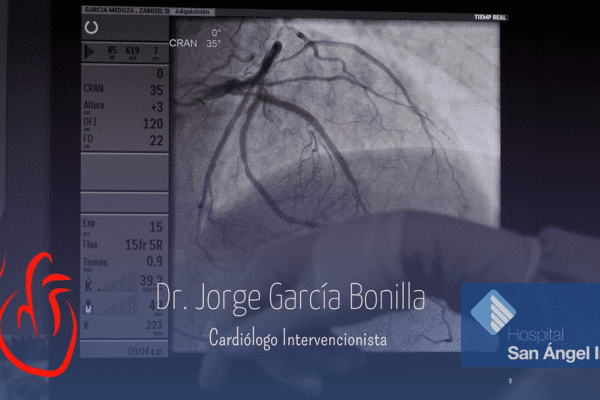

Conoce mis instalaciones y algunos casos de pacientes en mi